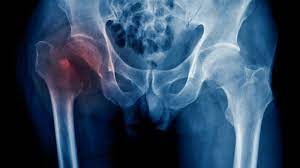

HIP FRACTURES

Hip is a joint where thigh bone (femur) meets with the hip (Acetabulum) bone. The “hip” is a ball-and-socket joint that allows the leg to bend and rotate at the pelvis.

TYPES OF FRACTURES

Intracapsular Fracture (Neck of femur)

Extracapsuar (Intertrochanteric or Subtrochanteric Fracture)